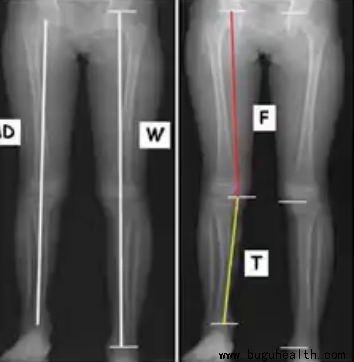

CT扫描——仰卧位

CT扫描是目前最准确的测量方法,可以精准测量出股骨和胫骨的长度,与传统的X射线相比辐射较少。但是不显示承重代偿,有辐射,昂贵,耗时,并非随时可用。

X射线——仰卧位

X射线相对准确可靠,可以显示人体代偿下肢不等长情况。但是它也存在辐射,不能提供股骨及胫骨具体的测量,同样也较昂贵、耗时,并非随时可用。

康复中心,长短腿